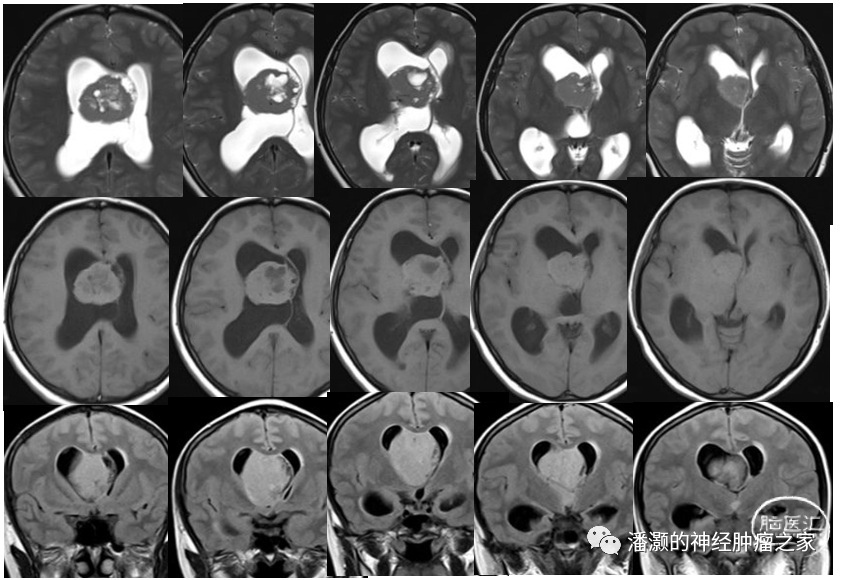

术后第三天复查头颅MR如下:

复查MRI提示两部位肿瘤均切除满意。未见明显肿瘤残留。

术后6天复查头颅CT观察脑室情况,基本同术前,无明显脑积水出现。